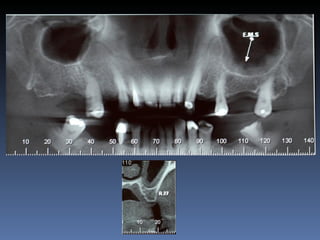

Diagnóstico:Desdentada parcial maxila

Plano de tratamento:      Reabilitação com 6 blocos

“onlay” provenientes de Úmero fresco-congelado

(FFB); reabertura para instalação de 6 implantes

dentários endo-ósseos e reabilitação protética fixa.

22-09-2011

20-04-2012

OPG Pré-op

Mensurações

Zona    Zona    Zona   Zona    Zona     Zona

1.6    1.3     1.1     2.1     2.3      2.6

Stage I       2,0mm   1,5mm 1,5mm 2,9mm 1,5mm         1,5mm

Pré-op (mm)

Stage I     6,5mm     7,0mm 7,1mm 5,2mm 6,7mm         7,0mm

Pós-op (mm)

Aument        4,5mm   5,5mm   5,6mm   2,3mm   5,2mm   5,5mm

o

Espessura

(mm)

Reabert       6,4mm   7,0mm   7,0mm 5,1mm     6,6mm   7,0mm

ura

Stage II

Reabsor       0,1mm   0,0mm   0,1mm   0,1mm   0,1mm   0,0mm

ção